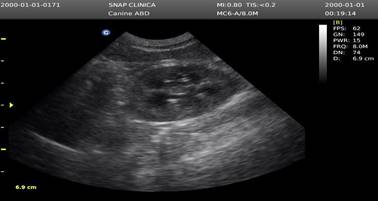

La Figura 2 indica presencia de espermatozoides en placa de orina al tratarse de un perro entero (no castrado), además, en la Figura 3 se observó prostatitis al momento de la ecografía, lo cual indica una inflamación de la próstata, datos complementarios a la patología principal.

Figura 3. Ecografía de la próstata (tamaño normal de la próstata con una ecogenicidad heterogénea entre los lóbulos prostáticos) Ecógrafo chison eco 3(INNOVAVET Riobamba -25 abril de 2025).